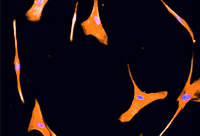

Células inflamatórias

Pesquisa sobre células neurais estuda como inibir processos inflamatórios no cérebro

(Texto: Instituto Biomédico)